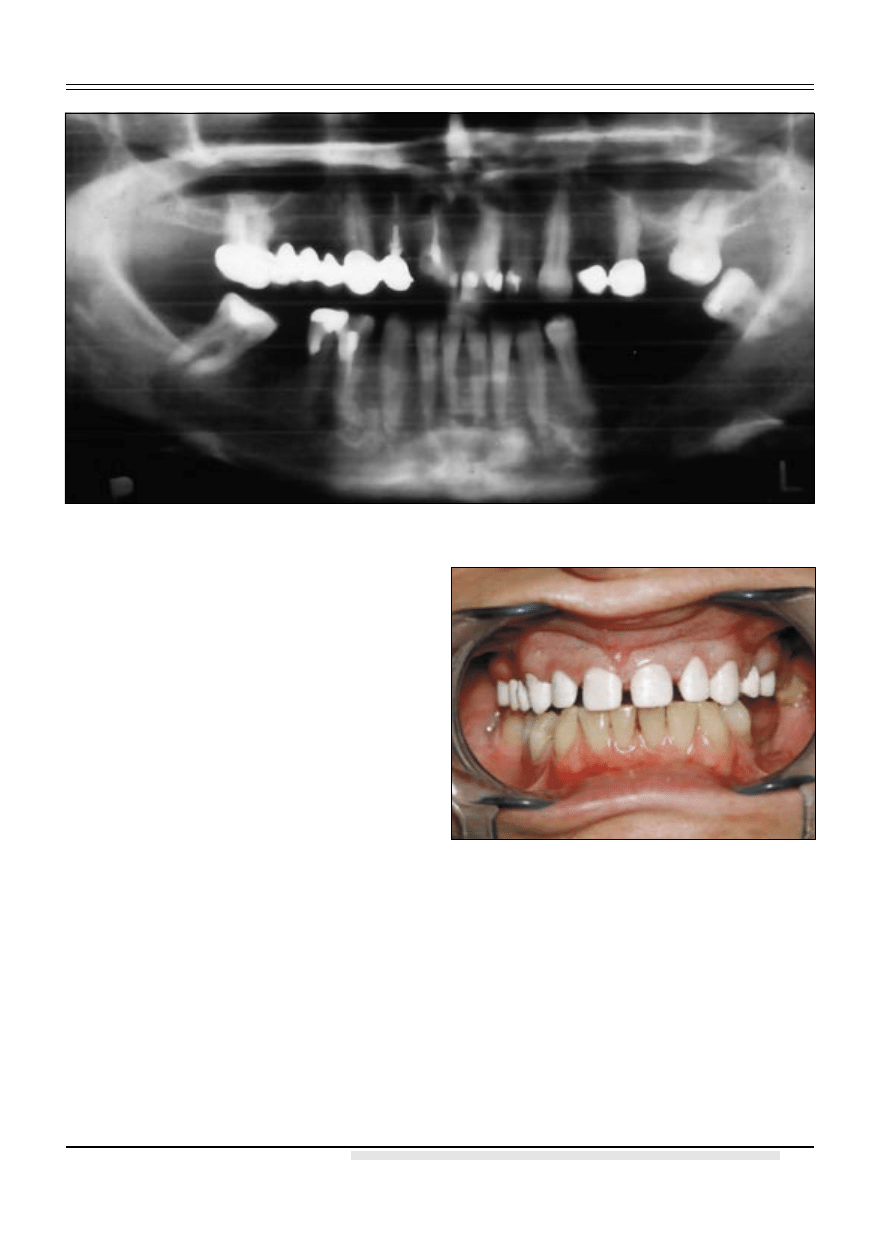

W ramach przygotowania przedprotetycznego

usunięto standardowy wkład koronowo-korze-

niowy z korzenia zęba 12. Przeprowadzono po-

wtórne leczenie endodontyczne zębów 11, 12, 17.

Zacementowano adhezyjnie na cement Variolink

II wkłady koronowo-korzeniowe standardowe

Glassix nr 3 i 4 w zęby 17 i 11. Na zniszczony

poddziąsłowo korzeń zęba 12 wykonano indy-

widualny wkład koronowo-korzeniowy ze stopu

złota, który zacementowano na cement glassjo-

nomerowy modyfikowany żywicą Fuji Plus. Ze

względu na liczne wypełnienia klasy III i IV w

zębach 11, 21 i 22 zdecydowano się na wykona-

nie pojedyńczych koron ceramicznych na podbu-

dowie z tlenku cyrkonu, w odcinkach bocznych

wykonano mosty z tego samego materiału w za-

kresie zębów 16-13-12 oraz 23-25. Podbudowę

wykonano w technologii CAD/CAM w systemie

firmy Wieland w kolorze białym, gdyż planowa-

no uzupełnienie w barwie A1 lub A2. (ryc. 3).

Należy w tym miejscu wspomnieć, iż struktura

cyrkonowa po wyfrezowaniu jest o około 25-

-33% większa od podbudowy docelowej, gdyż

po procesie synteryzacji następuje jej zmniejsze-

nie do ostatecznych wymiarów, jednakże znany

jest nam rodzaj cyrkonu nie zmieniający swo-

ich wymiarów po procesie synteryzacji, jest to

tzw. cyrkonia silikatowa (8). Gotowe uzupeł-

nienie zacementowano na cement kompomero-

wy Rely X Unicem. Następnie wybielono zęby

dolne pacjentki za pomocą szyny nakładkowej

z użyciem preparatu Opalescence 35% i 20%.

(ryc. 5 i 6) W dłuższej perspektywie zaplanowano

uzupełnienie rozległego braku międzyzębowego

Ryc. 2. Zdjęcie pantomograficzne.

Ryc. 3. Kontrola struktury z dwutlenku cyrkonu.

Ryc. 4. Model roboczy.